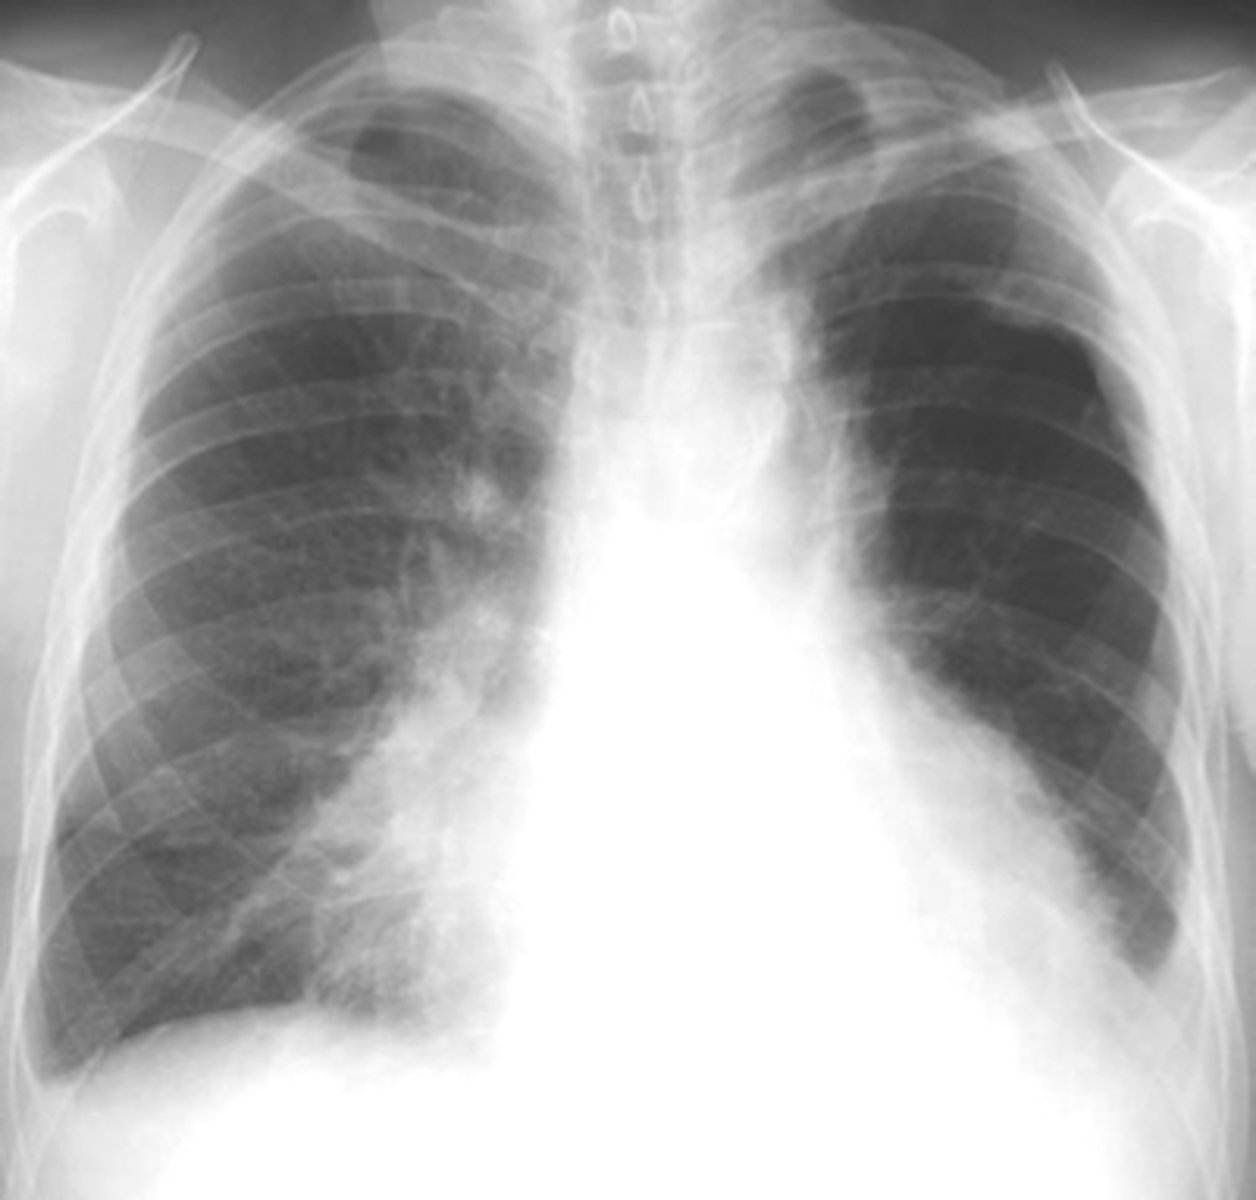

Bilateral interstitial infiltrates